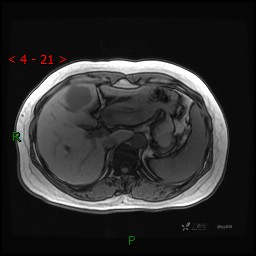

动态增强(动脉早期、动脉晚期、门脉期)